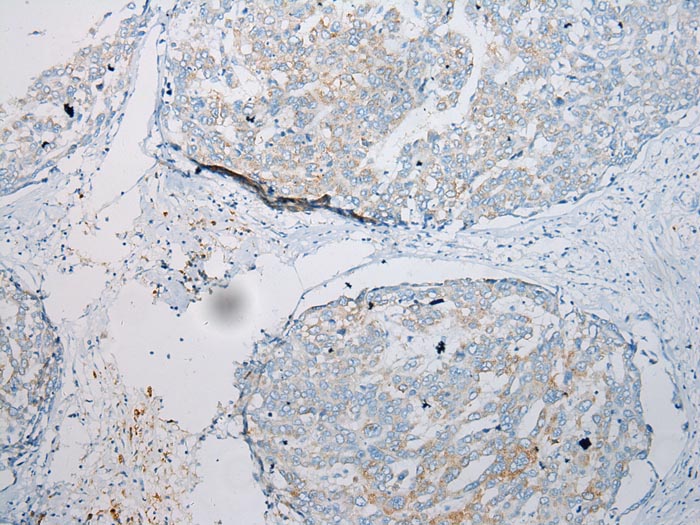

Immunohistochemical analysis of paraffin-embedded Human Liver cancer tissue using #43233 at dilution 1/200.